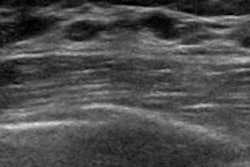

For example, researchers from Froedtert Hospital in Milwaukee, WI, found that morphologic features of axillary nodes on sonography are reliable indicators in predicting metastasis. Find out what these features are in this edition’s featured article.